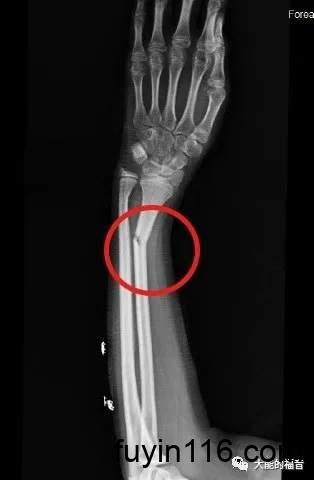

我们再举个例子让大家明白,比如一个人,他整天咳嗽,身体不舒服,然后呢,他手臂又痛,总是觉得痛,但不知道痛的原因在哪里,然后呢,就去医院看医生。

医生说,你手臂痛,头痛,而且摸着就痛,但是医生又不能把他的肉挖开了,看里面怎么样,所以医生说你去照下X光,一照X光,发现原来他里面的骨头断了。

他一照X光,发现骨头断了,请问是不是X光机把他骨头打断了?

不是的;

其实,他以前骨头就断了;而X光机把他已经骨折这件事显明出来了而已。

(上图来自网络)